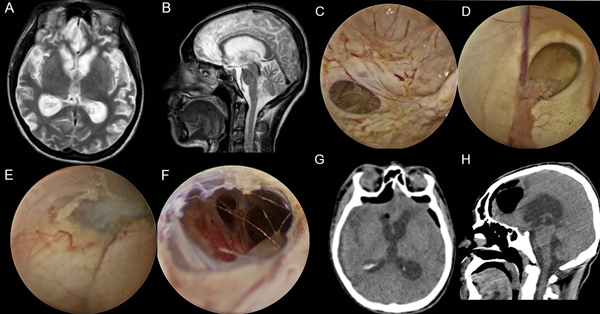

Se presentan en figuras 8 a 12 los casos ilustrativos más representativos de nuestra serie.

Figura 11: Hidrocefalia por obstrucción de la salida del IV ventrículo por quiste de Blake A-B) RM preoperatoria. C-F) Hallazgos intra-operatorios. G-H) RM cerebral postoperatoria.